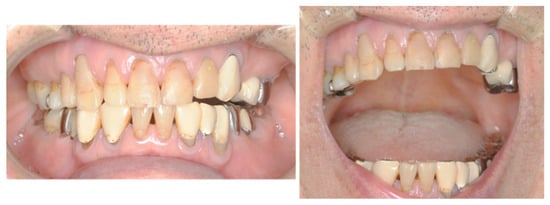

Clinical extra-oral examination revealed facial asymmetry and atrophy of the right masseter muscle (Figure 1), which was first observed in December 2012 by the primary care dentist before the patient presented to our department. However, the patient did not report any disorientation, trauma, dysphagia, or dysphonia. Intra-oral examination revealed normal occlusion with restricted mouth opening (20 mm) and associated mandibular deviation to the right. There were no signs of inflammation or infection.

Although the right-sided mandibular deviation during mouth opening persisted, the degree of opening improved to >40 mm, and the patient’s eating disorder disappeared entirely by 2015 (Figure 6). Annual CT conducted from 2015 to 2020 revealed no abnormal findings or progression in muscle atrophy.

Figure 6. The degree of mouth opening improved to >40 mm, while the right-side mandibular deviation observed during mouth opening persisted.